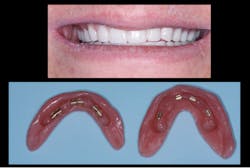

This next situation is a very common one when observing the current trend to oppose zirconia restorations on two edentulous arches without meticulous and knowledgeable occlusal equilibration. This can cause an implant or two to take the entire occlusal load, causing undue forces and stress on theAfter many decades of prosthodontic practice and hundreds of rehabs, I have found this an almost impossible and threatening technique. There is no articulator that can consistently mimic patient occlusion. Definitive occlusal equilibration is mandatory at seating, after a few weeks in the mouth, and subsequently on recare appointments (figures 4–6).